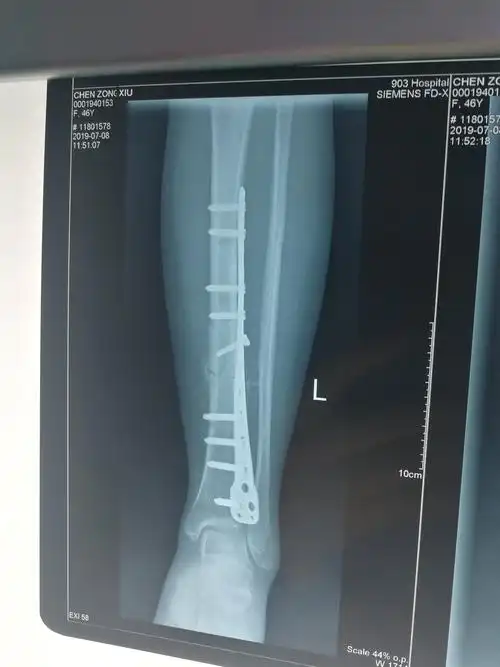

经过2个月的治疗后复查片可见骨折端对位对线良好,已有骨痂生成.

术后6个月见少量骨痂

见左胫骨骨折端为纤维组织填充,无连续性骨痂,无明显的炎性渗出物